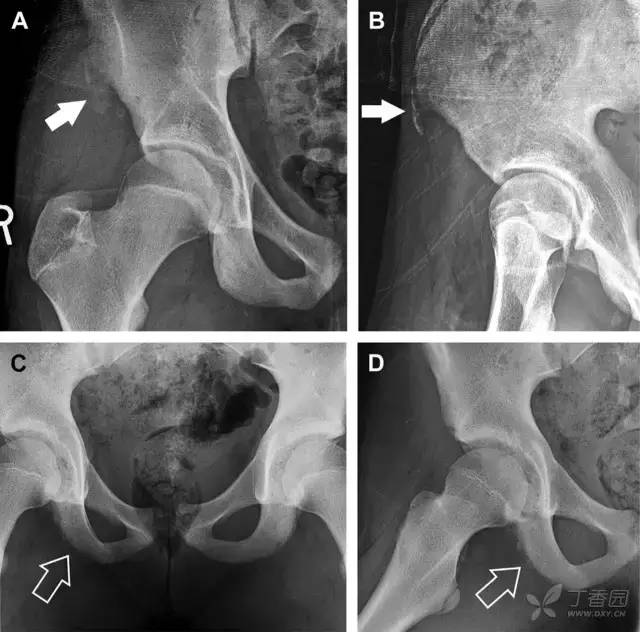

撕脱性骨折常在体育运动时由于肌肉强烈收缩引起。图 4 为容易发生儿童撕脱性骨折的部位。

图 5 儿童撕脱性骨折。正位片(A)和斜位片(B)示从髂前上棘撕脱的骨折碎片(箭头)。正位片(C)和另一个患者的蛙式位片(D)示右侧坐骨支皮质毛糙,腘绳肌腱撕脱损伤(如 C 和 D 空箭头所示)